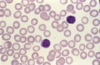

normal red blood cells

23

Q

A

normochromic, normocytic red blood cells

24

Q

A

peripheral blood smear